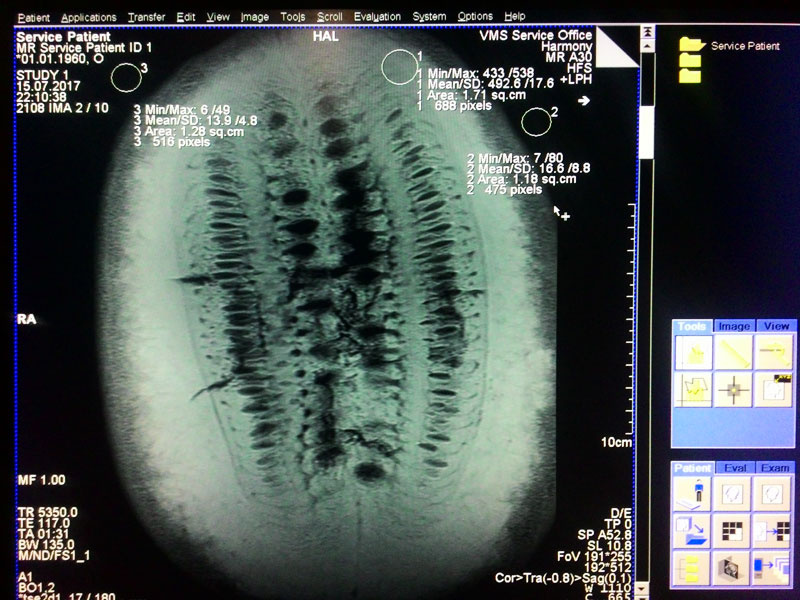

Арбуз готовится к исследованию. На нем сверху лежит катушка, предназначенная для грудной области, под ним — катушка для спинного отдела и позвоночника. Справа на полу — шар для предсказаний специальный объект для калибровки систем аппарата, так называемый «фантом»

Мало кто режет арбузы в поперечном направлении. Аппарат МРТ позволяет сделать это без ножа. Знали ли вы об интересной фрактальной структуре внутри? Обратите внимание, что верхняя часть, которая ближе к приемным элементам катушки светлее, так как амплитуда сигнала, получаемого из этой области выше, чем снизу ягоды.

Продольный разрез уже знаком всем. Думаю, арбуз спелый, можно брать.